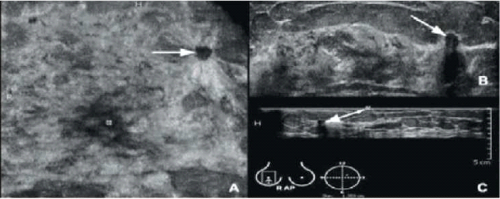

חסרונות הבדיקה: הבדיקה ארוכה יחסית ותלויה במידה רבה במיומנות המבצע. במחקר של Kolb[13] משנת 1998, נמצא שבבדיקת אולטרסאונד לנשים עם שד צפוף, שתוצאות בדיקת הממוגרפיה שלהן הייתה תקינה ניתן לאבחן עוד שלושה מקרי סרטן שד לכל 1,000 נשים. הגידולים שהתגלו באולטרסאונד לא היו שונים מבחינת גודלם והפיזור שלהם, לעומת הגידולים הלא-נמושים (שלא ניתן למשש אותם) שנמצאו בממוגרפיה.

במחקרים נוספים שבוצעו למשל על ידי קריסטל[14] או לקונט[15], נמצא שהאולטרסאונד הוא כלי יעיל בגילוי סרטן השד בנשים עם שד צפוף, במיוחד כאשר מדובר בנשים הנמצאות בסיכון גבוה לפתח מחלה זו. במחקר אחר שנערך על ידי החוקר Blume, 6666 Imaging Network ACRIN[16], נבדקו 2,809 נשים עם שד צפוף וסיכון מוגבר לפתח סרטן שד. נמצא, שהוספה של בדיקת אולטרסאונד מעבר לבדיקת הממוגרפיה, הביאה לגילוי מוגבר של סרטן השד, בשיעור של 1.1-7.2 מקרים, ל-1,000 נשים המצויות בסיכון. מאידך, שימוש בבדיקה זו עלול להגביר את שיעור התוצאות החיוביות השגויות (False positive result), דבר העלול לגרום לבדיקות מעקב רבות, ובדיקות ביופסיה מיותרות.